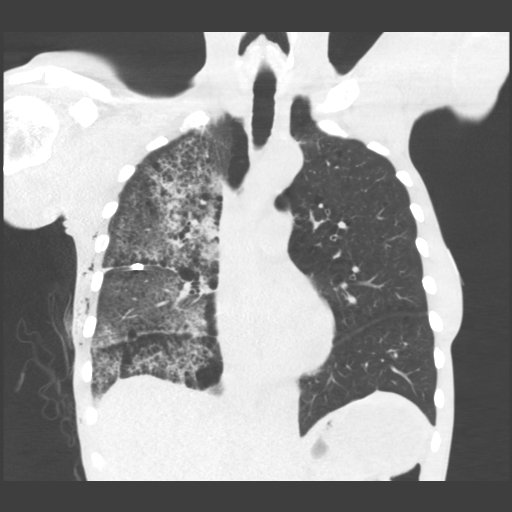

Re-expansion pulm. edema: rare important cause unilateral edema after (wait for it) rapid lung expansion after thoracentesis or PTX. Mortality up to 20%, prevent by removing < 1.5 L fluid. Complete recovery after < 1 week in this case. #chestraded #FOAMrad #FOAMed